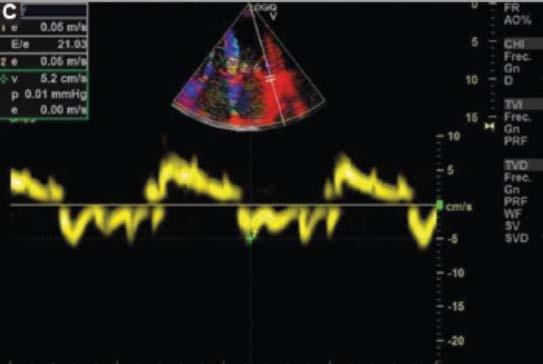

1. Evoluciona con clínica tórpida, desarrollando signos de IC por lo que se solicita electrocardiograma (Fig. 1), ecocardiograma Doppler color (Fig. 2) y resonancia magnética nuclear cardiaca. Esta última informa: ventrículo izquierdo no dilatado, leve incremento de espesor parietal septal (12 mm), fracción de eyección de ventrículo izquierdo: 51%. IM leve, AI moderadamente dilatada. Fibrosis difusa transmural inferoseptal basal e inferoseptal medial, fibrosis subendocárdica en pared inferior de ventrículo derecho. Valores de T1 mapping nativo aumentados en forma difusa (valores mayores a 1110 ms). Volumen extracelular (VEC) 55%, hallazgos compatibles con AC. Por referir palpitaciones se solicita estudio holter de 24 horas (Fig. 3).

Se diagnostica mieloma múltiple y AC con IC función sistólica preservada, iniciando tratamiento dirigido a ambas enfermedades. En su seguimiento presenta mejoría clínica de la función renal y cardiaca; luego de dos meses de tratamiento, las mediciones de NT-pro BNP y troponina I ultrasensible habían descendido un 30%. En ecocardiograma control se puede objetivar mejoría de la función diastólica, progresando desde una disfunción diastólica III (flujo transmitral tipo restrictivo) a una tipo I (flujo transmitral prolongado), mejoría en Doppler tisular y parámetros de deformación longitudinal global.

B

D

Figura 2. Ecocardiograma Doppler color. A: paraesternal 4 cámaras, hipertrofia concéntrica. B: deterioro de la función sistólica de ventrículo derecho evaluada por Doppler tisular. C: relación Doppler de flujo transmitral y Doppler tisular mitral lateral alterado. D: disfunción diastólica grado III. A

C

Ecocardiograma

Lo característico de esta enfermedad es que el infiltrado afecta aurículas y tabique interauricular, aumento simétrico del espesor parietal ventricular derecho e izquierdo con un aspecto brillante moteado tipo granular y sistema de conducción. Los cambios para comenzar a considerar el diagnóstico diferencial de AC son la relación Ee´ > 9.6, el volumen auricular izquierdo indexado y la disminución en la fracción de contractilidad miocárdica o fracción de acortamiento. Además, entre otros parámetros habituales pueden citarse el índice de excentricidad o espesor parietal relativo, ―ya que el fenotipo habitual en los pacientes con AC es de hipertrofia ventricular izquierda (HVI) concéntrica―, y el engrosamiento difuso valvar13.

Inicialmente, disminuye la complacencia auricular y aumenta la presión intraauricular, lo que lleva a que se ocupe menor tiempo tanto en el llenado ventricular como en el auricular. El descenso del llenado diastólico precoz es compensado por un enérgico llenado diastólico final, lo que, en estadios avanzados de la enfermedad, se traduce en una pseudonormalizacion del patrón. Por otro lado, otros autores han observado que la progresión de la enfermedad conlleva deterioro precoz de la diástole, pero no puede diferenciarse si este cambio se debe al envejecimiento normal celular. Es decir, que pueden observarse un patrón transmitral tipo pseudonormal, más habitual, o un patrón prolongado, el cual deberá diferenciarse de los cambios producidos por el envejecimiento. Otro aspecto a considerar es la afectación de la válvula mitral, ya que se ha observado una alta prevalencia de insuficiencia mitral que altera el patrón de llenado ventricular. Conforme avanza la enfermedad también se observan cambios en el patrón de las venas pulmonares. La evaluación de la función diastólica se correlaciona con la gravedad de la enfermedad y puede ser utilizada en su seguimiento14,15.